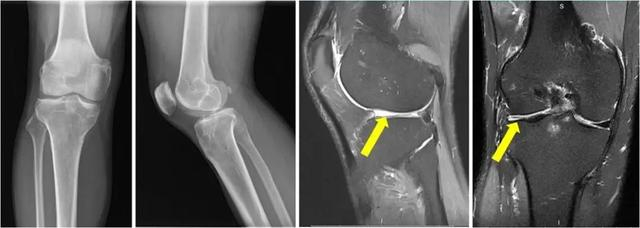

近期,同济大学附属同济医院骨关节外科中心程飚主任接诊了多位半月板缺失的年轻患者。患者冯某某,男性,41岁,4年前因右膝前交叉韧带断裂+半月板损伤,于当地医院行关节镜下右膝ACL重建术+半月板切除术。在半年前患者自觉右膝关节疼痛,活动时加剧,慕名来到上海市同济医院骨关节外科中心/运动医学科找到程飚主任团队,程飚主任经过仔细询问病情,全面查体后给予完善了右膝关节MRI,结果显示右膝关节外侧半月板缺失,外侧间隙狭窄,伴有轻度骨性关节炎出现。

术前影像学资料显示患者外侧半月板缺失,

外侧间隙狭窄